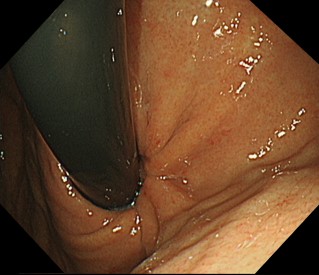

内視鏡で胃と食道のつなぎ目の粘膜を切除して、修復過程で狭くなることを利用して、逆流を防止します。